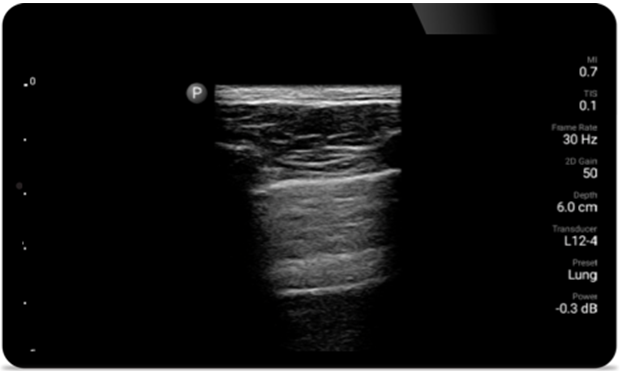

Breathe easier with

Lumify

Lumify can help assess patients faster and improve

accuracy when diagnosing common causes of

dyspnea and other lung conditions.